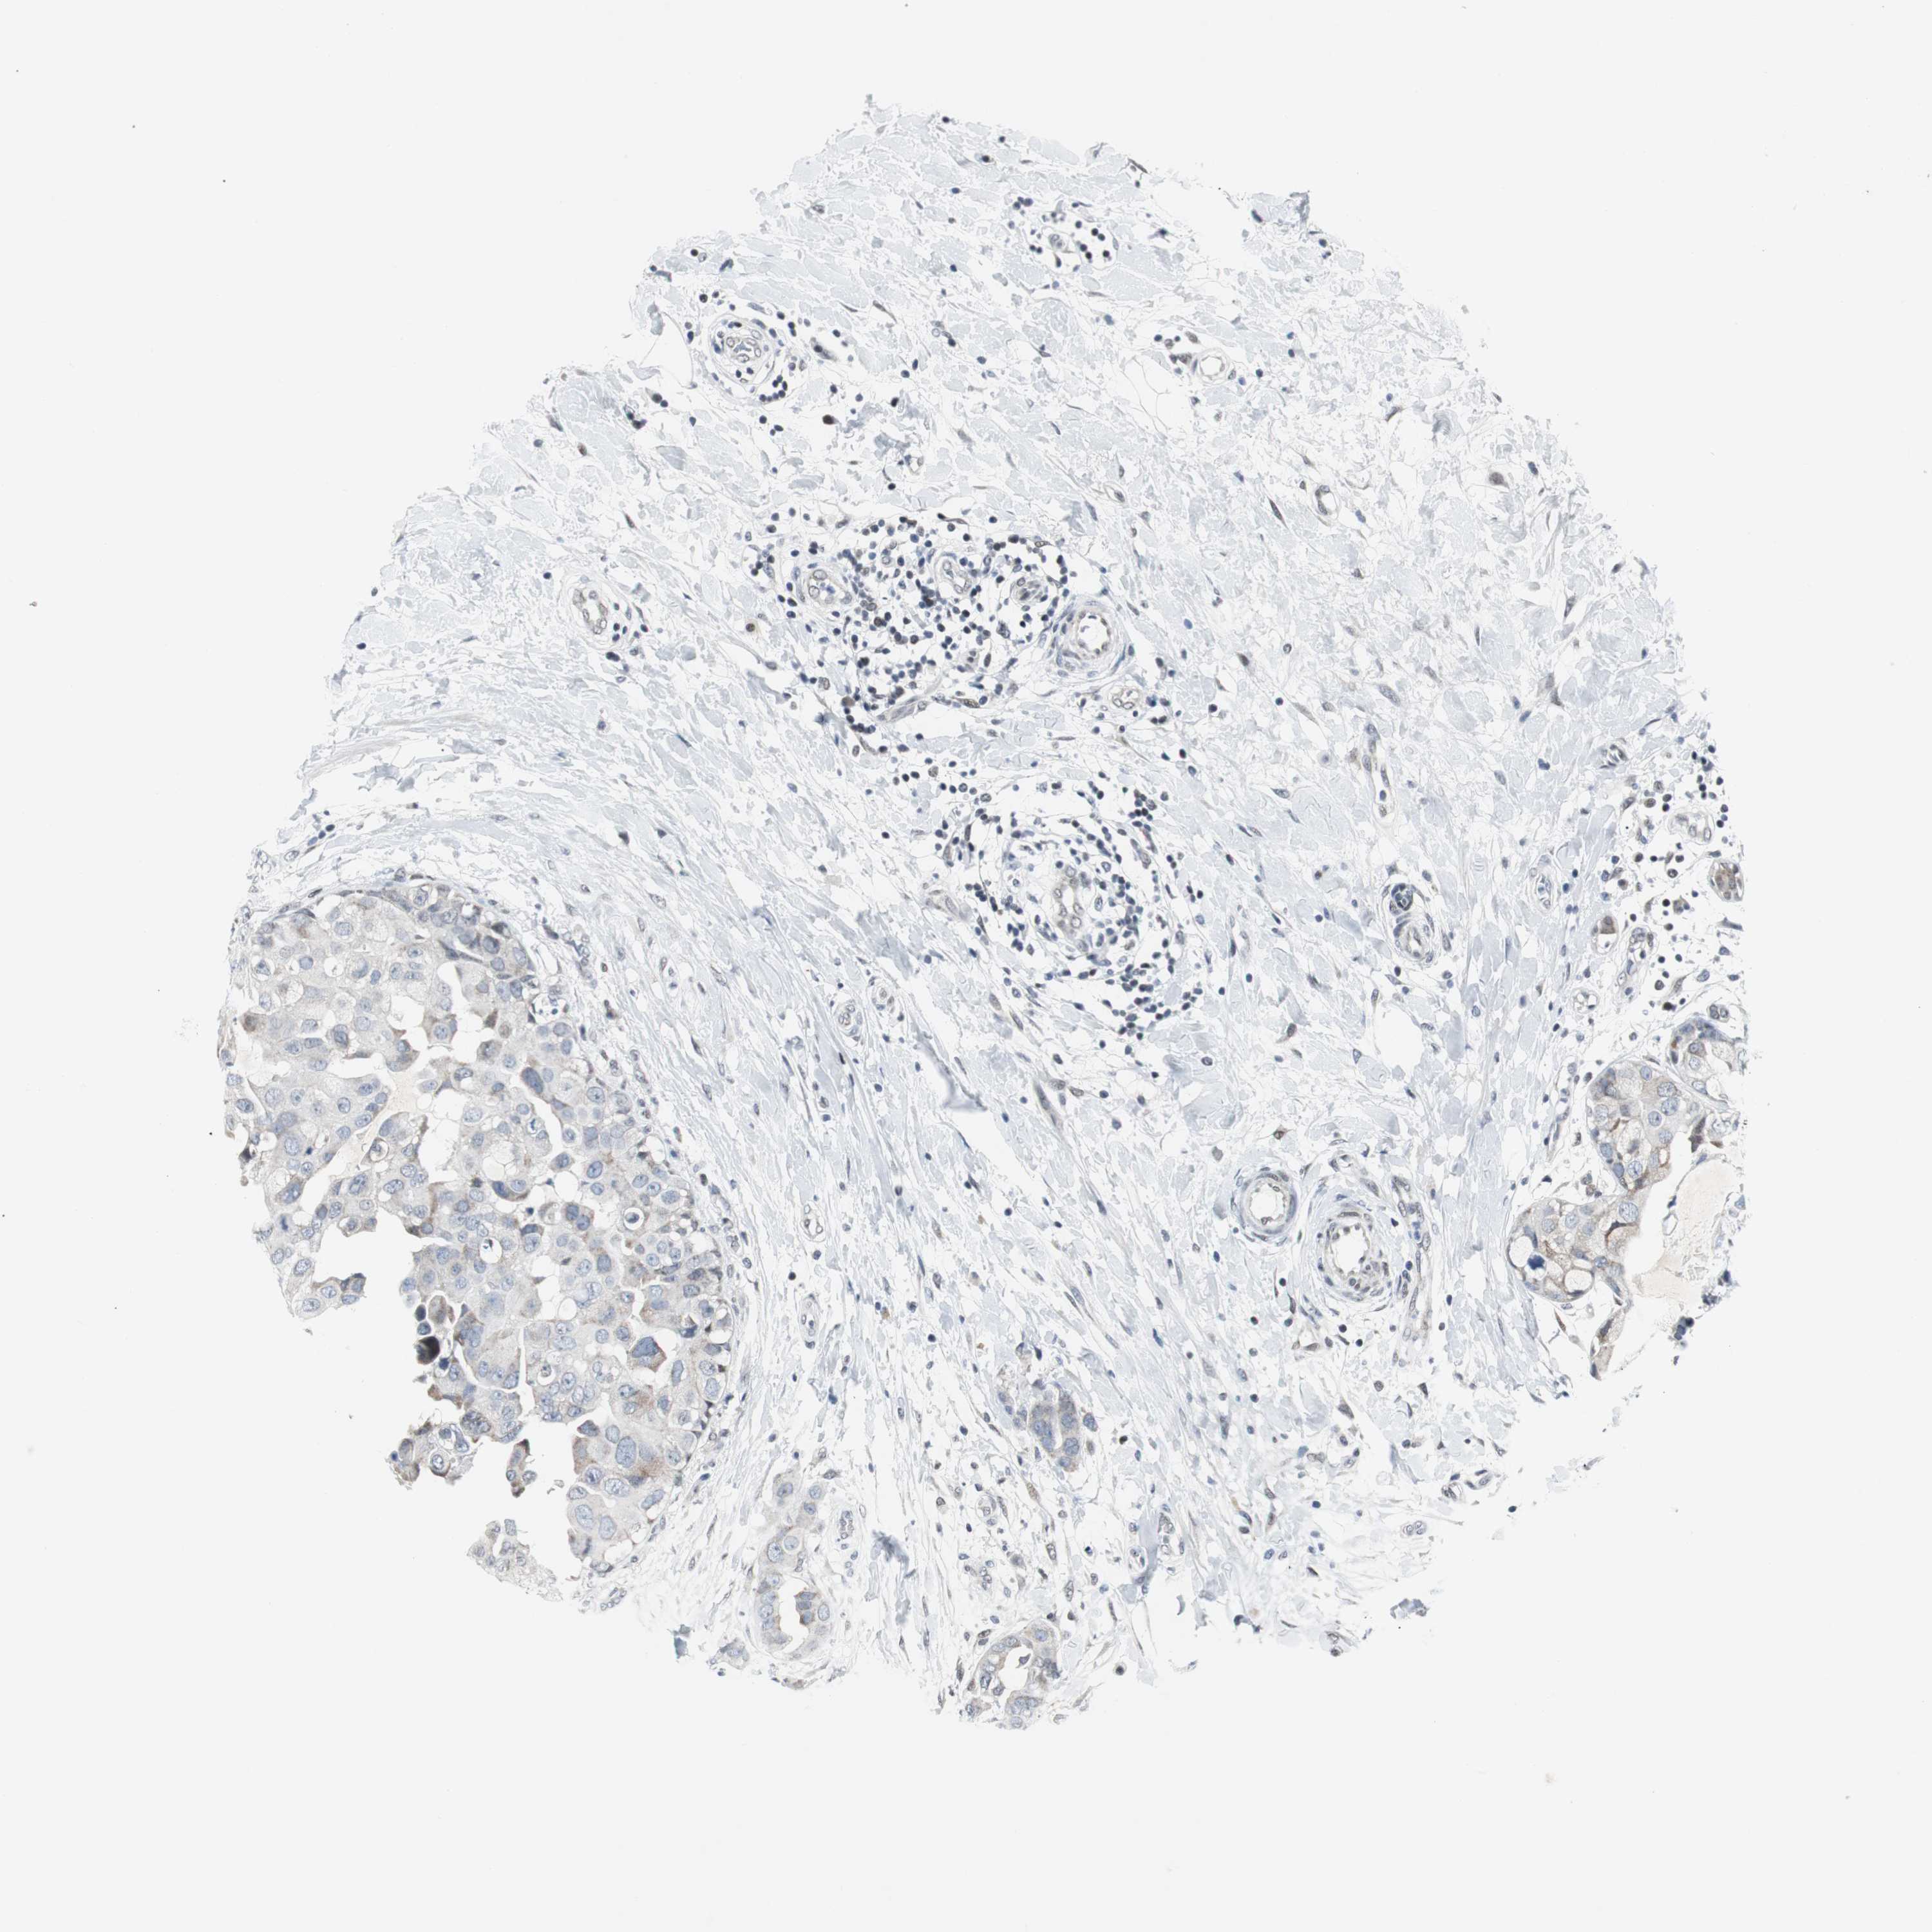

BRCA TCGA BRCA VALIDATION PROTEIN EXPRESSION